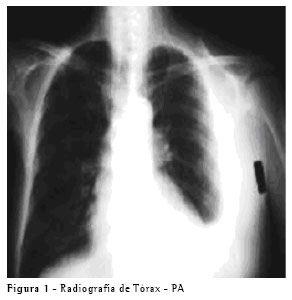

Paciente do sexo masculino, de 65 anos, procurou o Ambulatório de Doenças Pleurais do Hospital das Clínicas da Faculdade de Medicina da Universidade de São Paulo por orientação de seu cardiologista, com história de dispnéia e perda de peso. O paciente apresentava no seu histórico médico o diagnóstico de insuficiência cardíaca, e encontrava-se em vigência de tratamento adequado. Na propedêutica foram encontrados frêmito toracovocal e murmúrio vesicular diminuídos à esquerda e ausência de sinais de descompensação cardíaca. A radiografia de tórax mostrava um derrame pleural moderado à esquerda, sem alterações no mediastino (Figura 1). O paciente foi submetido a toracocentese, para alívio dos sintomas e com finalidade diagnóstica.